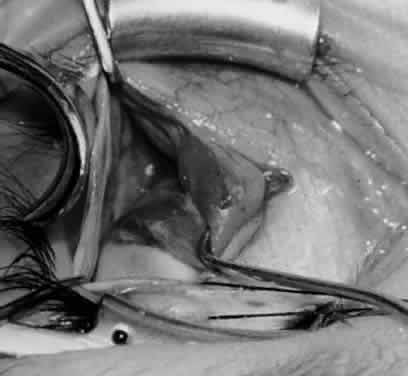

Fig. 5. The Stevens hook is placed adjacent to the posterior edge of the inferior oblique muscle and rotated as the inferior oblique muscle is drawn into the operative field. A forceps is used to retract the redundant Tenon's capsule, encapsulated fat, and intermuscular septum as the muscle is drawn further into the operative field with the Stevens muscle hook.

Fig. 6. The Westcott scissor is used to open the intermuscular septum along the posterior border of the inferior oblique muscle. Care is taken to cut adjacent to the tip of the Stevens muscle hook. This incision is important because it helps to avoid damaging the Tenon's capsule and releasing fat, which leads to the adherence syndrome and postoperative hypotropia.

Fig. 7. A Westcott scissor is used gently to open a space beneath the elevated inferior oblique muscle and allow placement of a Green muscle hook.

Fig. 8. The Green muscle hook is placed beneath the belly of the inferior oblique muscle, and the eye is retracted nasally.

Fig. 9. A Westcott scissor is used to dissect the intermuscular septum and expose the insertion of the inferior oblique muscle.

Fig. 10. The inferior oblique muscle is placed on the Green muscle hook. The exposed insertion is ready for myotomy, myectomy, disinsertion, placement of sutures for recession, or removal for the extirpation procedure.